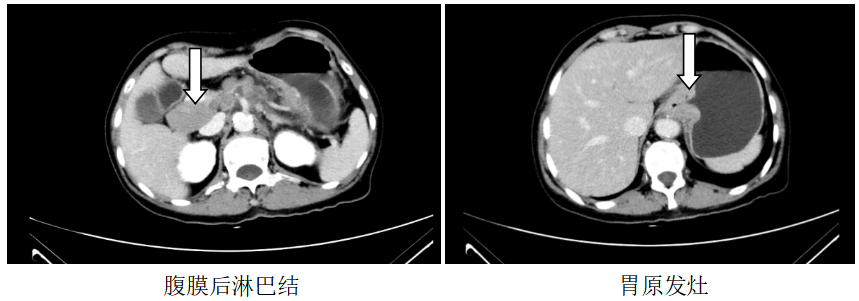

颅脑MR:左侧额、枕叶脑转移瘤;

胸部CT:1、左锁骨区、左腋窝多发肿大淋巴结,考虑转移,建议随访,全腹CT:考虑食管胃交界癌累及胃周脂肪并腹腔腹膜后淋巴结多发转移(CT分期约T4aN3)。

图1.2019.7.5影像(基线评估)

诊断:食管胃交界腺癌腹腔、腹膜后、左腋窝、左锁骨区淋巴结转移脑转移(cT4aN3M1,IV期,HER2扩增,MSS,PD-L1-)